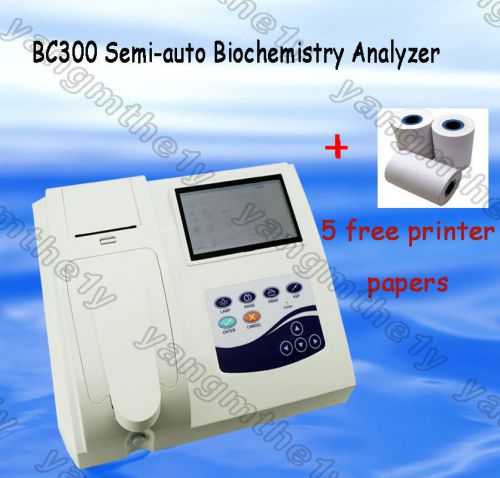

CE Semi-auto Biochemistry Analyzer,touch screen analyzing blood/body fluid